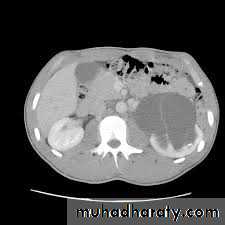

CTTreatment